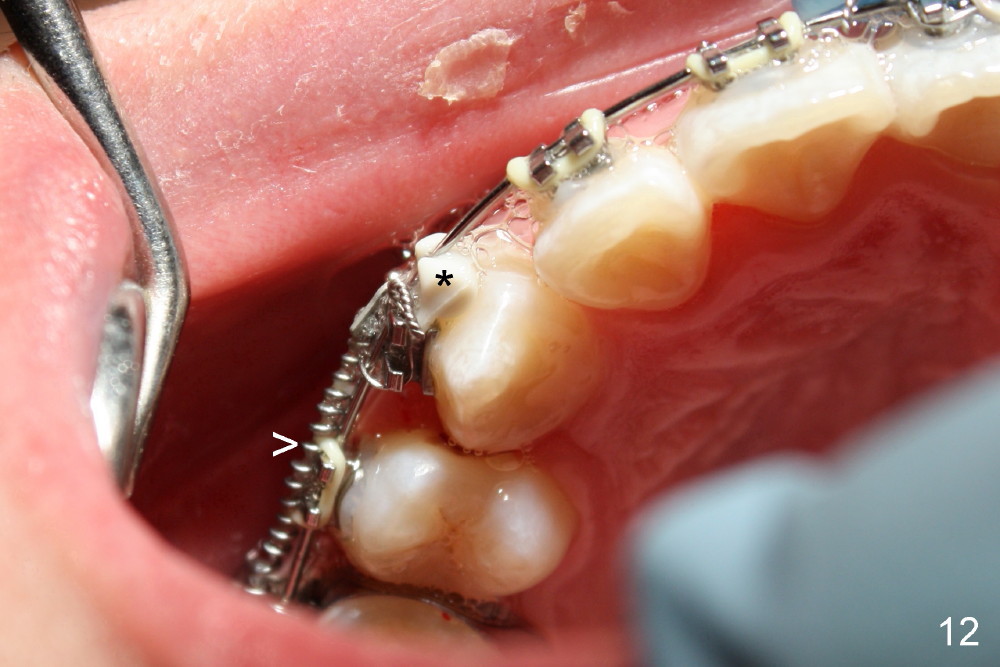

One month of closed coil spring (150 gms-9mm) (Fig.10 >, mirror image) results in the closure of the space between UR3 and 5. At the same appointment, there is enough space for UL 2 (Fig.11, mirror image). Notice the rotation of UR 3 due to retraction of the closed coil spring (Fig.10). It is immediately corrected when a rotation wedge is placed on the mesial of UR3 (Fig.12 *). However, there is an instant separation of UR 3 and 5. The closed coil spring has to be used (Fig.12>).